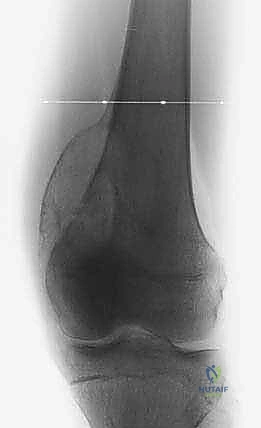

- الأشعة السينية (X-ray): الخطوة الأولى لتقييم العظام وتحديد نمط التدمير العظمي.

- الرنين المغناطيسي (MRI): هو المعيار الذهبي (Gold Standard) لتقييم الأورام. يوضح بدقة امتداد الورم في النخاع العظمي والأنسجة الرخوة، وعلاقته بالأعصاب والأوعية الدموية.

- الأشعة المقطعية (CT Scan): ضرورية لتقييم القشرة العظمية والتكلسات داخل الورم، وللبحث عن أي انتشار في الرئتين.

يعتمد الأستاذ الدكتور محمد هطيف على دراسة هذه الصور الإشعاعية شخصياً قبل تحديد مسار إبرة الخزعة، لضمان عدم تلويث الحجرات العضلية السليمة (Compartments).

الحالة الأولى: إنقاذ ركبة رياضي شاب

شاب يبلغ من العمر 19 عاماً عانى من ألم مستمر في الركبة وتورم لم يستجب للمسكنات. بعد الفحص السريري الدقيق وإجراء الرنين المغناطيسي، اشتبه الأستاذ الدكتور محمد هطيف بوجود ورم. تم إجراء خزعة إبرة أساسية دقيقة جداً. أظهرت النتائج وجود "ساركوما عظمية" في مراحلها الأولى. بفضل الخزعة الدقيقة التي لم تلوث الأنسجة المحيطة، تمكن الدكتور هطيف لاحقاً من استئصال الورم بالكامل وتركيب مفصل صناعي خاص بالأورام، مما أنقذ ساق الشاب من البتر ومكنه من العودة للمشي بشكل طبيعي.